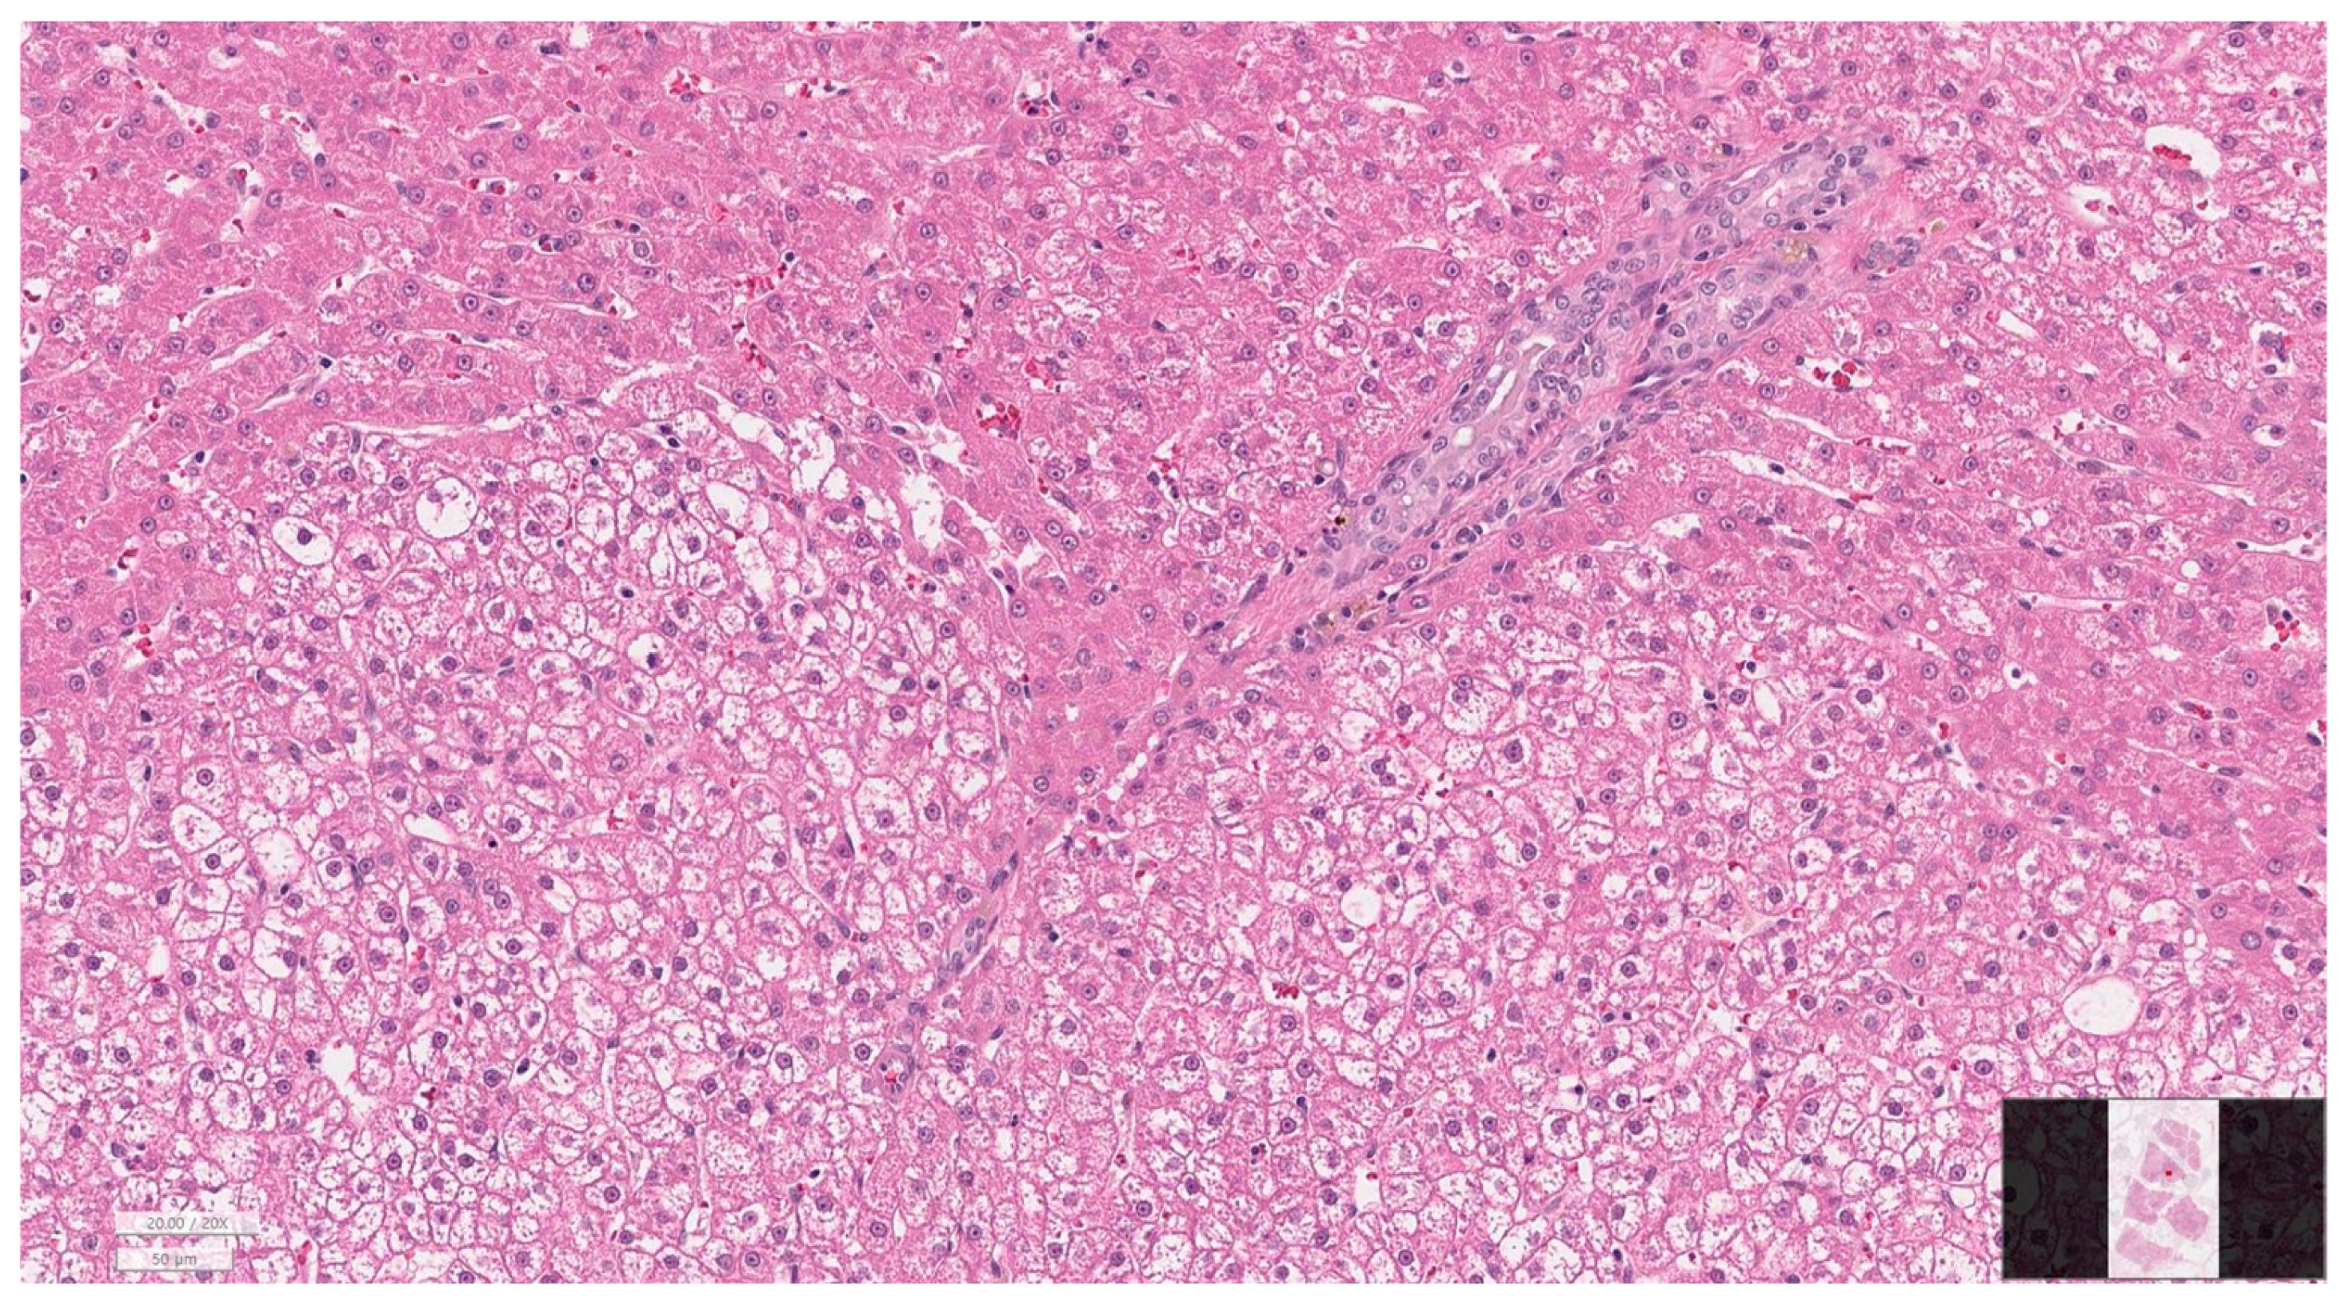

2.7. Histopathological Evaluation

3.6. Histopathology of Gallbladder and Liver